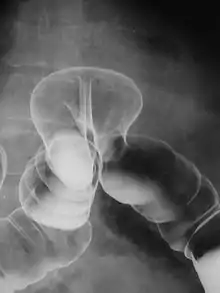

Lavement baryté en double contraste montrant une hernie transdiaphragmatique du côlon.